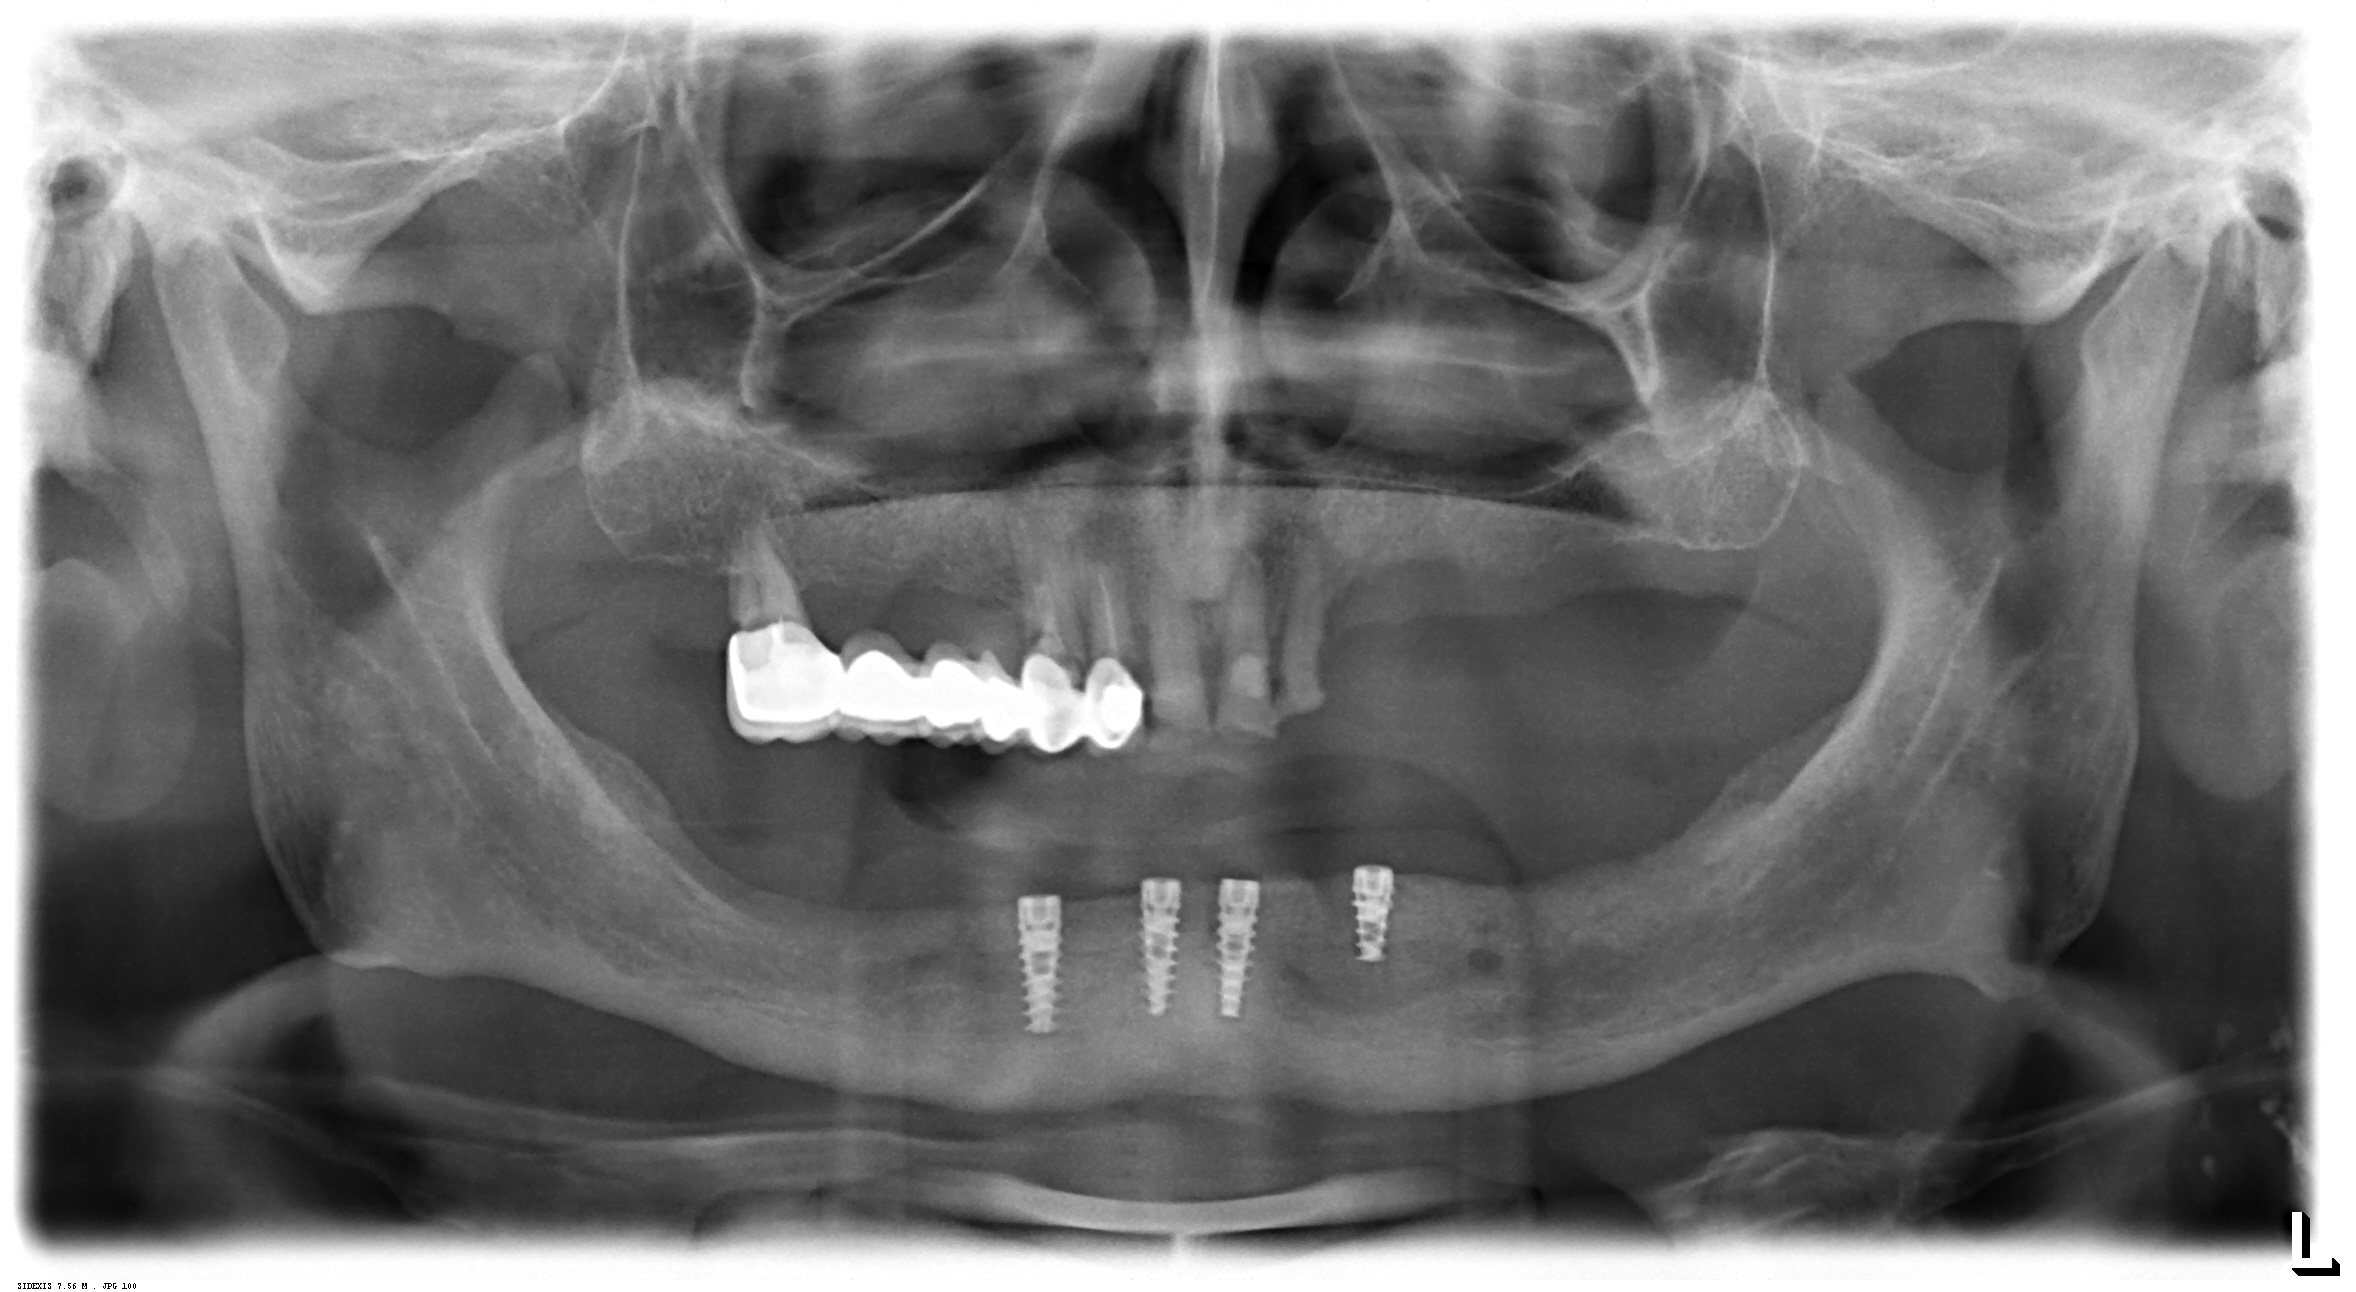

Όπως είναι γνωστό πως οι ακτινογραφίες παίζουν ένα σημαντικό ρόλο στη διάγνωση και αναγνώριση αρκετών οδοντιατρικών προβλημάτων. Στο ιατρείο του Dr. Νίκου Δεικτάκη υπάρχει το σύστημα ψηφιακής ακτινογραφίας. Με το σύστημα αυτό ένας μικρός αισθητήρας χρησιμοποιείται αντί του κλασσικού φιλμ.

Ο αισθητήρας είναι συνδεμένος σε έναν υπολογιστή, έτσι ώστε όταν η ακτινογραφία καταγράφεται η εικόνα εμφανίζεται στην οθόνη σε δευτερόλεπτα. Ένα μεγάλο πλεονέκτημα του συστήματος της ψηφιακής ακτινογραφίας είναι η μειωμένη έκθεση στην ακτινοβολία. Επειδή ο αισθητήρας είναι πολύ ευαίσθητος η έκθεση μειώνεται στο 1/10 σε σχέση με την παλαιότερη μέθοδο με το κλασσικό φιλμ. Ένα δεύτερο μεγάλο πλεονέκτημα είναι η ταχύτητα με την οποία εμφανίζεται η ακτινογραφία στην οθόνη του υπολογιστή, κερδίζοντας πολύτιμο χρόνο.

Επίσης, ο ίδιος ο ασθενής μπορεί να δει την ακτινογραφία σε υψηλή ανάλυση και να κατανοήσει καλυτέρα το πρόβλημα του. Οι ακτινογραφίες αποθηκεύονται και ο οδοντίατρος μπορεί κάθε στιγμή να τις ξαναδεί αν χρειαστεί. Η ευκολία λήψης, απεικόνισης και αποθήκευσης των ακτινογραφιών καθιστά την ψηφιακή ακτινογραφία σε ένα πραγματικά ισχυρό εργαλείο, και σε συνδυασμό με την ικανότητα του οδοντιάτρου δίνει άριστα αποτελέσματα σε πολλές θεραπείες των δοντιών και των ουλών.